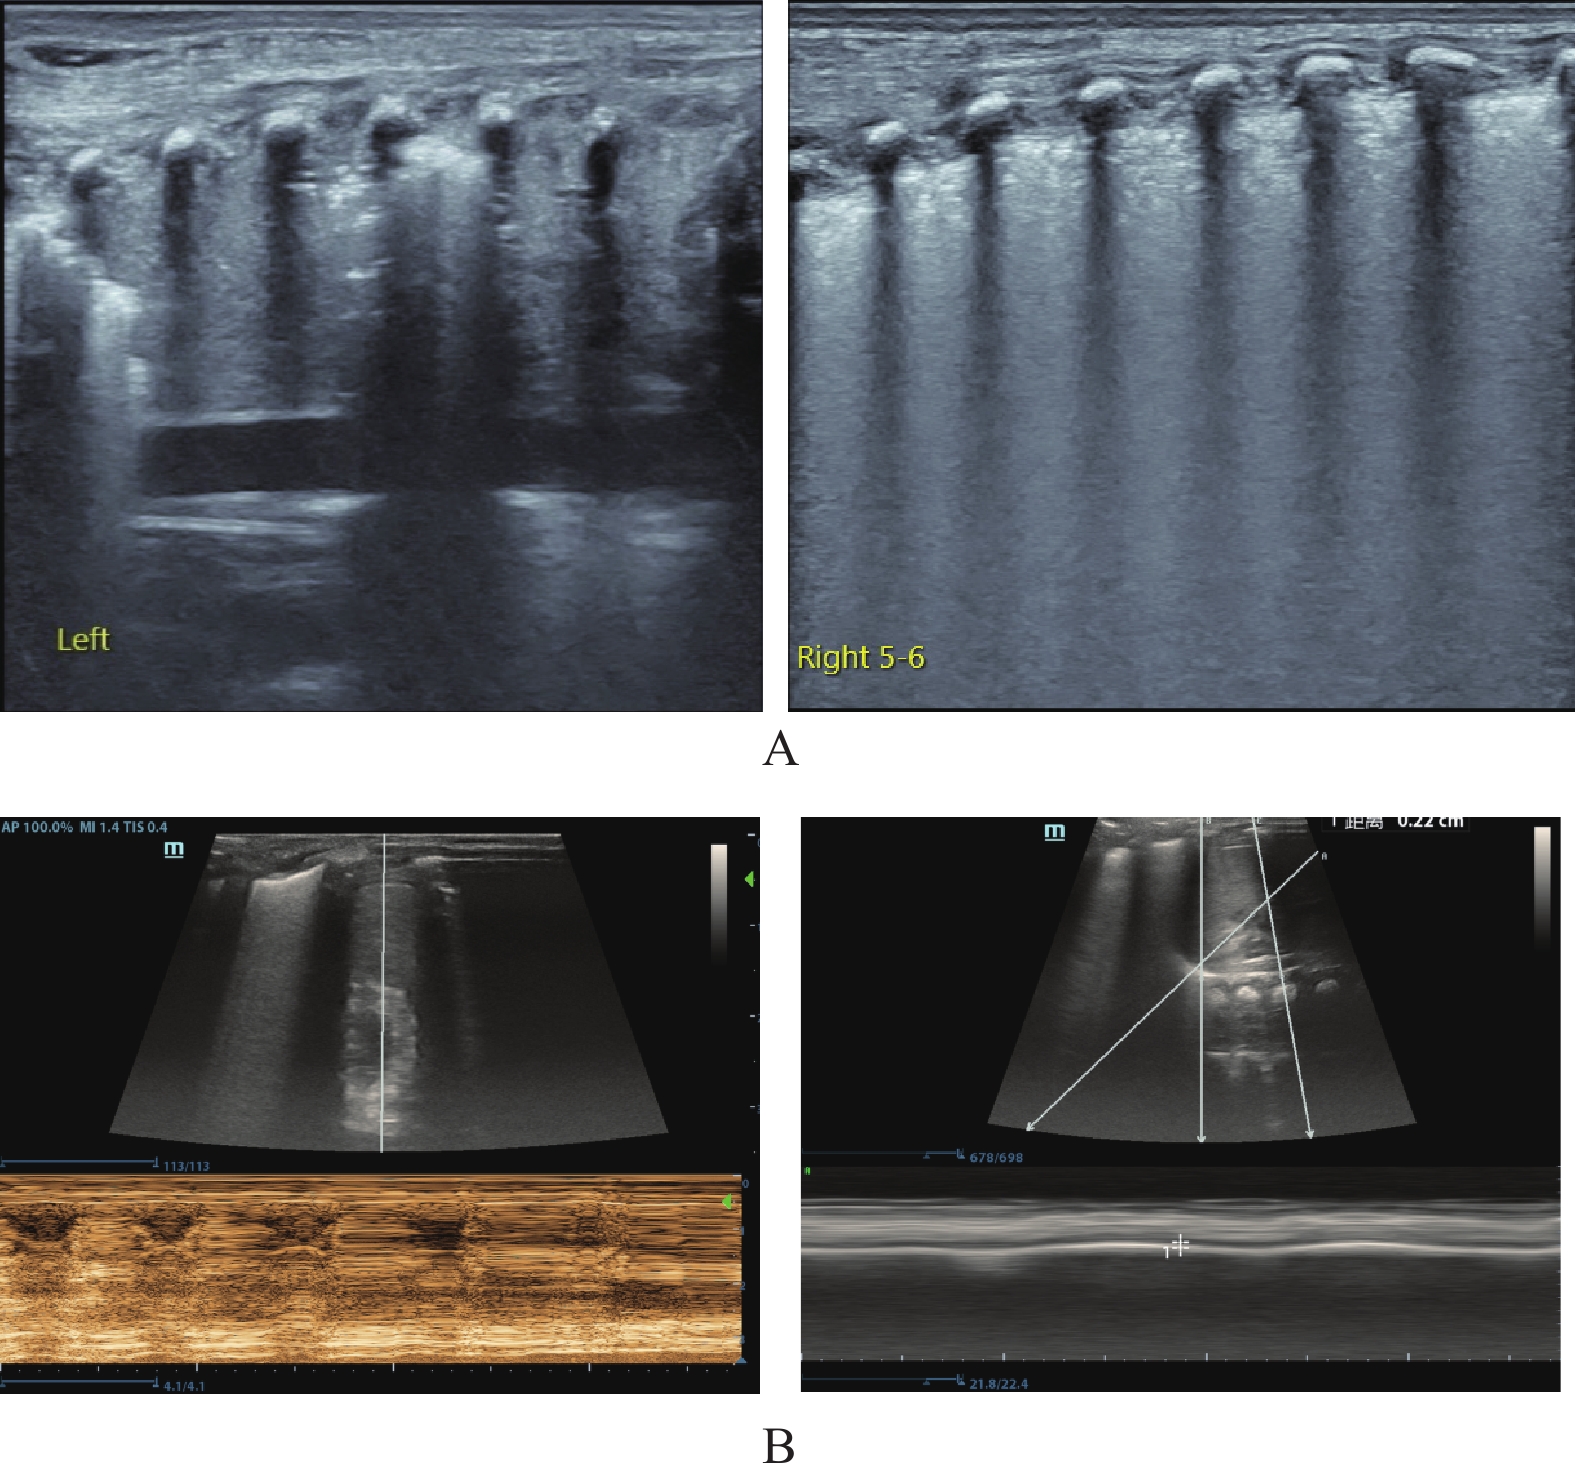

目的 探究肺部超声评分(LUS)、膈肌超声联合常规指标预测小儿重症肺炎(SP)并发急性呼吸窘迫综合征(ARDS)的价值。 方法 选取2022年8月至2023年8月昆明市儿童医院SP患儿160例,均行肺部超声、膈肌超声检查获取LUS、膈肌超声参数[膈肌移动度(DM)、膈肌厚度变化率(TF)],根据SP患儿住院期间是否并发ARDS分为ARDS组67例和非ARDS组93例,比较两组入院时一般资料、血清炎症因子水平、LUS、膈肌超声参数,分析SP患儿并发ARDS的影响因素,并分析LUS、膈肌超声参数预测SP患儿并发ARDS的价值。 结果 SP患儿住院期间ARDS发生率为41.88%(67/160);ARDS组入院时APS、APACHEⅡ评分、血清C反应蛋白(CRP)、白介素-6(IL-6)、高迁移率族蛋白B1(HMGB1)水平、LUS、DM高于非ARDS组,TF低于非ARDS组(P < 0.05);入院时APS、APACHEⅡ评分及血清CRP、IL-6、HMGB1水平、LUS、DM、TF均为SP患儿并发ARDS的影响因素(P < 0.05);LUS、DM、TF预测ARDS的曲线下面积(AUC)分别为0.718、0.742、0.720;常规预测方案(入院时APS、APACHEⅡ评分及血清CRP、IL-6、HMGB1水平联合)的AUC为0.852,新预测方案(常规预测方案基础上联合LUS、DM、TF)的AUC为0.930,新预测方案的AUC明显大于常规预测方案的AUC(P < 0.05)。 结论 LUS、膈肌超声参数DM、TF与SP患儿并发ARDS显著相关,联合常规指标可为临床预测SP患儿并发ARDS提供可靠依据。 Abstract:Objective To explore the value of lung ultrasound score (LUS) and diaphragm ultrasound combined with routine indicators in predicting the occurrence of acute respiratory distress syndrome (ARDS) in children with severe pneumonia (SP). Methods A total of 160 patients with SP were selected from Kunming Children’s Hospital from August 2022 to August 2023, all of whom underwent lung ultrasound and diaphragm ultrasound examination to obtain LUS and diaphragm ultrasound parameters [diaphragm mobility (DM), diaphragm thickness change rate (TF)]. The patients with SP were divided into ARDS group and non-ARDS group according to whether they were complicated with ARDS during hospitalization. The general data, serum inflammatory factor levels, LUS and diaphragm ultrasound parameters were compared between the two groups at admission, and the influencing factors of ARDS in children with SP were analyzed, and the value of LUS and diaphragm ultrasound parameters in predicting ARDS in children with SP was analyzed. Results The incidence of ARDS in SP patients was 41.88% (67/160). APS, APACHEⅡ scores, serum C-reactive protein (CRP), interleukin-6 (IL-6), high mobility group protein B1 (HMGB1) levels, LUS and DM in ARDS group were higher than those in non-ARDS group, TF were lower than those in non-ARDS group (P < 0.05). APS, APACHEⅡ scores, serum CRP, IL-6, HMGB1 levels, LUS, DM, TF were the influencing factors of ARDS in SP children at admission (P < 0.05). The area under the curve (AUC) of LUS, DM and TF predicted ARDS were 0.718, 0.742 and 0.720, respectively. The AUC of the conventional prediction scheme (APS, APACHEⅡ score combined with serum CRP, IL-6 and HMGB1 levels at admission) was 0.852, while that of the new prediction scheme (combined with LUS, DM and TF based on the conventional prediction scheme) was 0.930. The AUC of the new prediction scheme was significantly higher than that of the conventional prediction scheme (P < 0.05). Conclusion LUS, DM, TF, and SP parameters of the diaphragm are significantly correlated with ARDS in children with SP, and the combination of routine indicators can provide reliable evidence for clinical prediction of ARDS in children with SP. -

组别 n LUS(分) DM(cm) TF(%) ARDS组 67 20.15±3.26 1.41±0.34 37.24±3.65 非ARDS组 93 17.48±2.51 1.12±0.28 41.08±4.13 t 5.852 5.905 6.087 P <0.001* <0.001* <0.001* *P < 0.05。 表 3 SP患儿并发ARDS的影响因素分析

变量 β SE Wald OR 95%CI P 下限 上限 APS 0.275 0.097 8.024 1.316 1.185 1.462 <0.001* APACHEⅡ 0.207 0.075 7.618 1.230 1.129 1.340 <0.001* CRP 0.251 0.089 7.925 1.285 1.164 1.418 <0.001* IL-6 0.301 0.098 9.409 1.351 1.201 1.519 <0.001* HMGB1 0.233 0.084 7.676 1.262 1.150 1.385 <0.001* LUS 0.380 0.112 11.487 1.462 1.302 1.641 <0.001* DM 0.318 0.096 10.946 1.374 1.228 1.537 <0.001* TF −0.118 0.041 8.243 0.889 0.813 0.972 <0.001* *P < 0.05。 表 4 LUS、膈肌超声参数预测SP患儿并发ARDS的价值

Table 4. Value of LUS and diaphragm ultrasound parameters in predicting ARDS in children with SP

指标 AUC 95%CI 截断值 敏感度(%) 特异度(%) LUS 0.718 0.641~0.786 19.02分 68.66 69.89 DM 0.742 0.668~0.809 1.33 cm 73.13 75.27 TF 0.720 0.644~0.788 38.50% 64.18 73.12 表 5 不同预测方案的预测SP患儿并发ARDS的价值比较